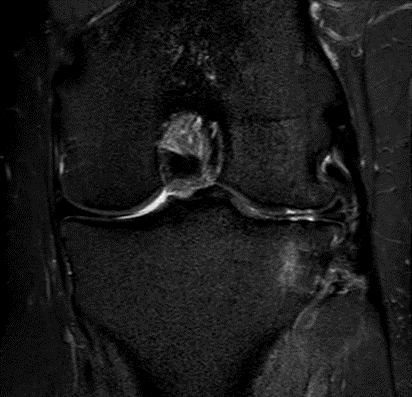

MRI scans illustrating the improvements regarding Group 2 are presented below, showing pre-treatment images with evident cartilage defects, pronounced bone marrow edema, and synovial inflammation, followed by post-treatment scans demonstrating improved joint structure, reduced edema, and decreased inflammation (Figures 12-29).

Figure 18: Female, 77 years, pre-intervention MRI.

Figure 19: Female of figure 18, two-month follow-up MRI: MSC plus ChondroFiller® liquid.